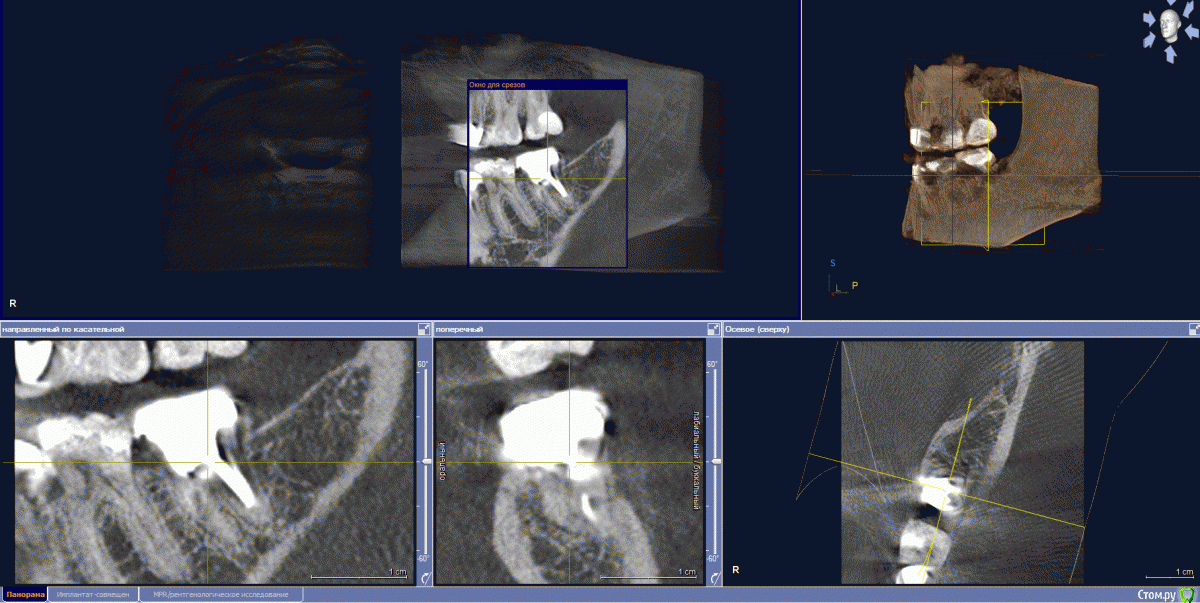

Jaz Опубликовано 23 сентября, 2017 Поделиться Опубликовано 23 сентября, 2017 (изменено) Здравствуйте!Итак, имеется в наличии зуб 47 (или 37? в общем, нижняя левая семерка). Года три как депульпирован, установлена вкладка и металлокерамика (материалы не знаю). По КТ нашли кариес под коронкой и кариес корня, т.е. 100% удаление.Жевательных зубов у меня и так прискорбно мало. Хочу ставить имплант. Но начиталась таких ужасов про имплантацию, что хотела бы собрать мнения знающих людей, прежде чем начинать сию операцию. совершенно запуталась в обилии информации. 1) одномоментная или классическая? Зуб еще на месте, и, как я поняла, лучше ставить имплант сразу после того, как зуб выдерут? Никаких заболеваний у меня вроде нет (но может нужно какие анализы сдать и провериться? на диабет меня не проверяли просто)2) нужна ли в моем случае подсадка кости или какие-то иные манипуляции, требующие затрат (планирую брать кредит, момент важный)3) у меня глубины и ширины кости вообще для имплантации хватает? или мне морально готовиться к вставной челюсти в 30 лет?3) прочитала здесь на форуме, что на нижние семерки сразу нагрузку не дают. Но разве это не приведет к деградации кости?4) какой производитель все же лучше? Насчет коронки, как я понимаю, лучше цирконий? Я работаю с химикатами (формалин, ксилолы, фиксаторы и вся прочая патологоанотомическая каша) - есть в этом случае какие-то нюансы в выборе материала для штифта и коронки? Прилагаю снимки КТ. Толком не поняла, как их в программе делать. Если что - переделаю. Изменено 23 сентября, 2017 пользователем Jaz Ссылка на комментарий

колесников Опубликовано 23 сентября, 2017 Поделиться Опубликовано 23 сентября, 2017 (изменено) Здравствуйте! В вашем случае предпочтение к одномоментной имплантации. (Костной ткани достаточно для первичной стабильности импланта,но есть тенденция к образованию узкого гребня после удаления). Из дополнительных расходов будет:удаление зуба,0.5 г кости,возможно пересадка лоскута десны,установка формирователя десны.Систему лучше выбирать совместно с вашим доктором. Изменено 23 сентября, 2017 пользователем колесников Ссылка на комментарий

IvanK Опубликовано 2 октября, 2017 Поделиться Опубликовано 2 октября, 2017 По Вашим снимкам общей картины не понять Если есть мнение... то нужно до начала лечения обратиться к ортодонту для консультации Ссылка на комментарий